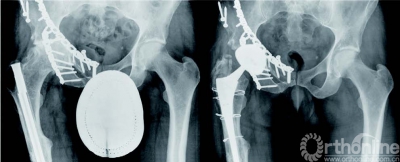

其余398 名患者(343髋) 平均随访7.0 ±3.1(2.0—14.2) 年。手术时平均年龄为42±7.3(17-50) 岁。210 例THA(60%) 是在男性。术前诊断包括原发性骨关节炎或股骨髋臼撞击引起的髋关节疼痛(173髋,49%),DDH(123髋,35%),股骨头坏死(20 髋,6%),创伤性关节炎(20 髋,6%)和其它(14 髋,4%)( 表 1,图2和3)。60 髋(17%)曾接受过手术(表1),包括股骨和骨盆截骨术(30髋,9%),切开复位内固定(8 髋,2%) 和其他手术(22 髋6%) ( 表1)。本研究通过伦理委员会审批,所有患者均签署知情同意书。

既往报道年轻患者全髋关节置换术后效果欠佳。归因于活动量大,引起磨损、骨溶解和假体断裂。由于年轻患者预期寿命长,这些问题尤为突出。在一般人群中,氧化铝陶瓷对陶瓷界面磨损和骨溶解极小。本研究则表明氧化陶瓷对陶瓷髋关节置换对于年轻活跃人群也甚为可靠。术后平均随访7年未见任何磨损所致骨溶解的影像学表现非常值得称道,因为骨溶解是THA 失败的最常见原因。一例(1髋,0.3%) 使用骨水泥柄的患者出现了骨溶解,已计划行翻修手术。术后14年后因假体失败再手术的累计无再次手术率为98.1%(CI,96.5-99.6%),因任何原因再手术的无再次手术率为97.2%(CI,95.4-99.0%)。该结果与使用相同设计假体的老年患者相当。本研究患者中还包括了35%的DDH和17%的既往接受过手术的病例,这两类患者出现并发症和失败的几率较高。